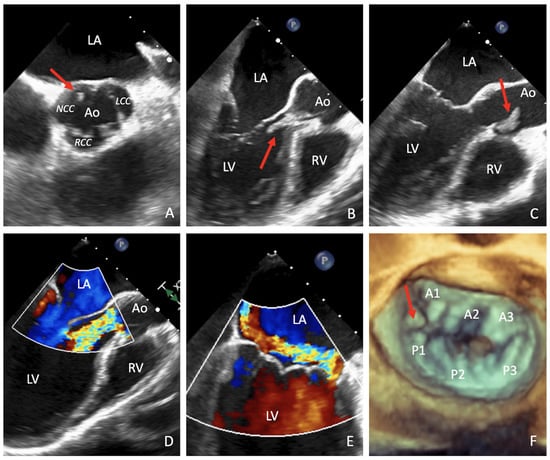

A 50-year-old man with no co-morbidities presented with pneumonia after unsuccessful empirical treatment at home with levofloxacin 750 mg/day. The patient was first admitted in the pneumology department, but the main infectious disease analyses (H1N1, HIV, quantiferon, and legionella-pneumococcal-mycoplasma antigens), as well as the first nasopharingeal swab test for SARS-CoV-2 results were negative. Due to the sudden development of heart failure, the patient was transferred to the cardiac-ICU, where a trans-oesophageal echocardiography (TOE) showed a tricuspid aortic valve affected by endocarditis, with multiple motile vegetations above the cusps (the major one of 2 × 0.5 cm2 on the non-coronary cusp), resulting in severe aortic regurgitation (AR) (Figure 1 and Supplemental Video S1). A concomitant severe mitral regurgitation (MR) due to prolapse/flail of the myxomatous antero-lateral scallop of the posterior leaflet (P1) and a mildly reduced left ventricle ejection fraction (LVEF) (50%) were also observed. Later, a second SARS-CoV-2 nasopharyngeal swab test result was positive and a total-body computed tomograpy (CT) scan confirmed the presence of a COVID-19 pneumonia, with bilateral apical and midfield ground glass pattern (Figure 2A and Supplementary Video S2), with hepatic and also splenic endocarditis embolizations. The patient was initially treated with i.v. 2 g vancomycin and 360 mg gentamicin daily, followed by 700 mg of daptomycin and 3 g meropenem per day, although the first six sets of blood culture results were negative. The presence of abundant pleural effusion required percutaneous bilateral drainage, while high-dose inotropic support and non-invasive ventilation (NIV) with continuous positive airway pressure (CPAP, 10 cmH2O, FIO2 0.6) were started due to progressive hemodynamic and respiratory deterioration, obtaining adequate gas exchange, thus, avoiding the need for orotracheal intubation (OTI) and prone positioning [5,6]. Then, the patient was transferred from the spoke unit (Sant’Anna Hospital, Como) to the central hub (San Raffaele University Hospital, Milan), since urgent surgery was indicated, despite increased surgical risk (STS, 4.8%) [1,7]. Here, after exclusion of QT interval abnormalities, immunomodulation therapy against SARS-CoV-2 with hydroxychloroquine 200 mg twice a day was added [8]. Contemporarily, the patient underwent an aortic valve replacement with a 23 mm Perimount bioprosthesis (Edwards Lifesciences Inc., Irvine, CA, USA) and a concomitant mitral valve repair with an antero-lateral para-commissural edge-to-edge (A1-P1) technique and a 37 mm Simulus partial flexible posterior prosthetic ring (Medtronic Minneapolis, MN, USA). Extra-corporeal circulatory (crystalloid Custodiol cardioplegia) and aortic cross-clamp times were 96 and 83 min, respectively. The patient entered the hub hospital in a dedicated COVID-19 pathway, which consisted of a specific COVID-19 negative pressure OR, with a postoperative stay reserved in the COVID-ICU/ward. In addition, healthcare personnel directly involved were required to use specific protections (i.e., FFP2/3 mask) to prevent droplets/contact transmission.

Figure 1.

Pre-operative trans-oesophageal echocardiography (TOE). Four-chambers TOE showing a motile vegetation (red arrow) on the non-coronary cusp of the aortic valve (A) during diastole (B) and systole (C), resulting in severe aortic regurgitation (AR) (D); Color doppler (E) and four-dimensional (4D) TOE (F) reported a concomitant severe MR due to P1 flail.